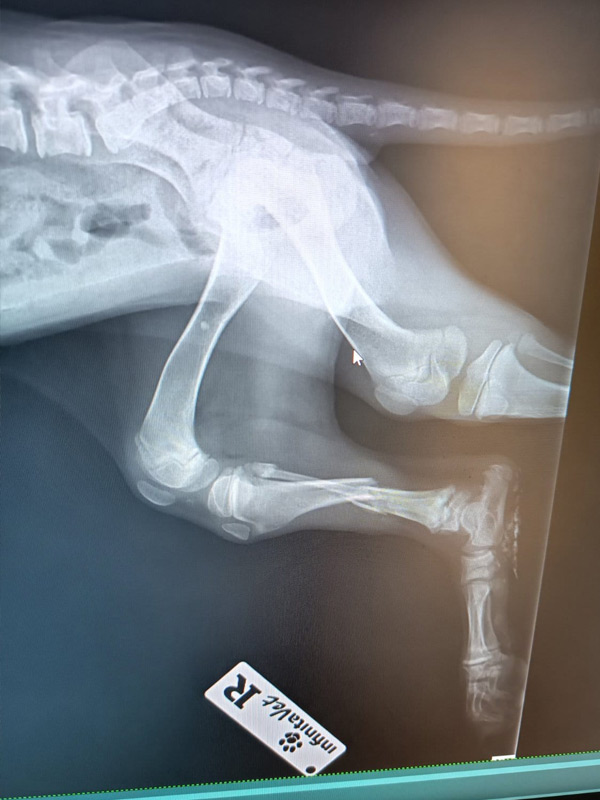

Zum Glück wurde Luca gefunden und sofort in eine Tierklinik gebracht. Dort folgte die erschütternde Diagnose: Ein Vorderbein und ein Hinterbein sind gebrochen. Die Röntgenbilder bestätigten das ganze Ausmaß ihrer Verletzungen.

Die Fraktur am Hinterbein kann ohne Operation ausheilen, hier ist strenge Schonung ausreichend.

Doch das Vorderbein ist so schwer verletzt, dass eine Operation dringend notwendig ist. Um eine stabile und dauerhafte Heilung zu ermöglichen, muss ein Metallimplantat eingesetzt werden. Nur so hat Luca die Chance, später wieder schmerzfrei zu laufen und ein normales Hundeleben zu führen.